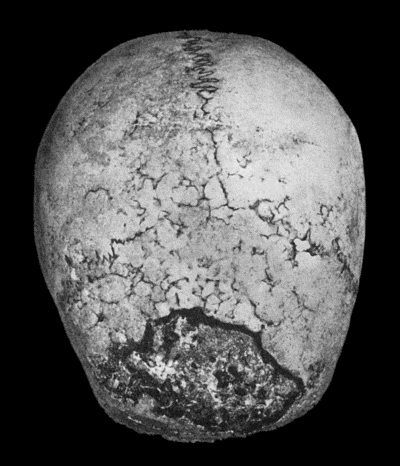

130.Syphilitic Disease of Skull 463

131.Syphilitic Hyperostosis and Sclerosis of Tibia 464